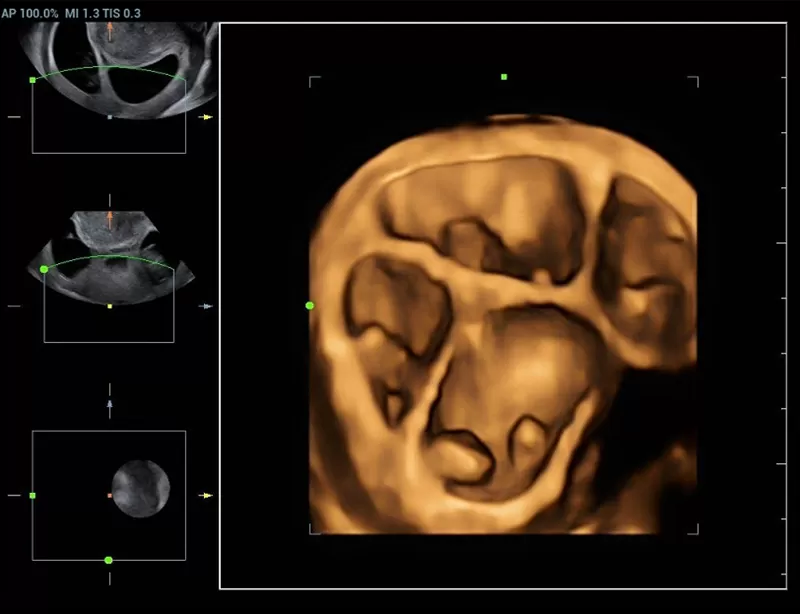

The innovative technologies:

- New iLive with Hyaline

- Smart face

- HD Scope

deliver a unique diagnostic tool for health services